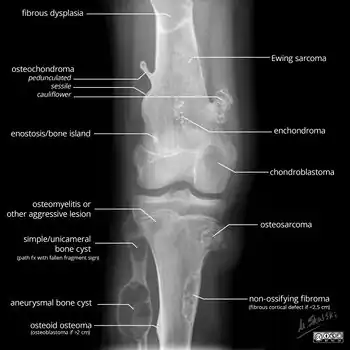

A bone tumor may be felt on examination, following which a plain X-ray is usually carried out.[4][13] Imaging is interpreted with the location of the lesion and the person's age being taken into account.[14]

X-ray appearances of different types of bone tumors in < 30 years. -